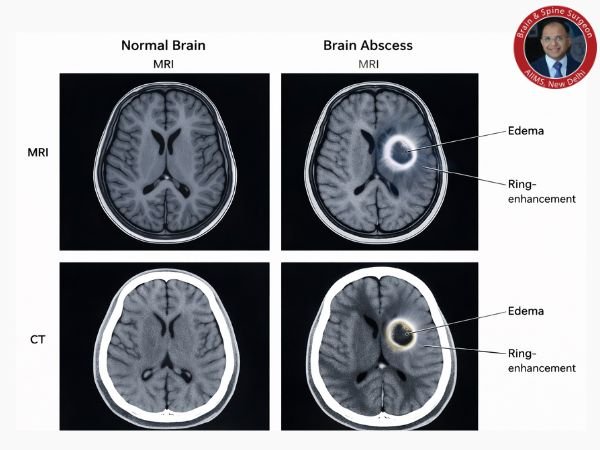

2. Imaging of the Brain

The most sensitive test is a brain MRI.

Brain CT Scan

These aid in the detection of pus accumulations, abscess formation, and swelling.

Brain infection is shown by MRI/CT.